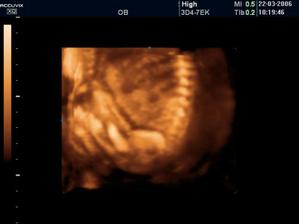

Náš pokladík Viktorko sa narodil 28.7.2006 o 19:20. Vážil 3650 g a meral 52 cm 😉.